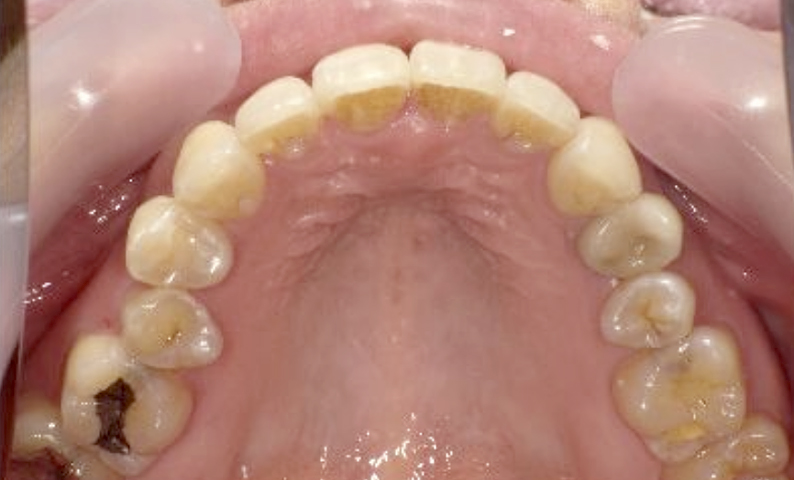

症例_003 下顎だけの部分矯正

治療期間:10ヶ月金額:24万円+税女性前歯のガタガタ下の前歯だけ上顎は補綴治療中